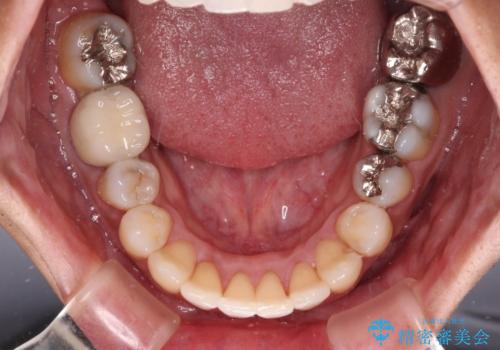

受け口傾向の咬み合わせ 前歯のデコボコをワイヤー矯正で素早く改善

- 前歯の見た目を気にして来院された患者様です。

ワイヤー矯正でもマウスピース矯正でも対応可能とお伝えし、非常に悩まれていましたが、2年後に転勤の可能性が高いとのことで、治療終了までの期間を想定しやすいワイヤー矯正にて治療を行うこととしました。

前歯のクロスバイトは、改善の途中で歯髄壊死を起こすリスクが高くなるため、マウスピース矯正よりもワイヤー矯正をお勧めしております。

この患者様もクロスバイトはあっという間に改善され、1年強で速やかに治療を終えることができました。